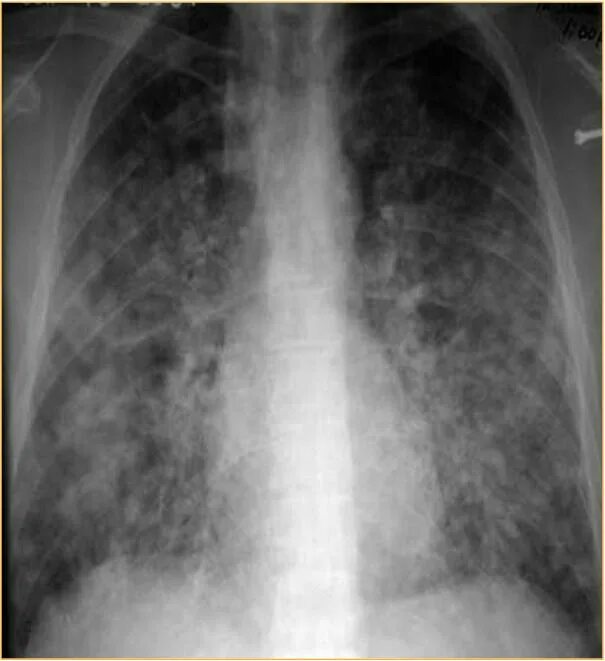

Гистоплазмоз это